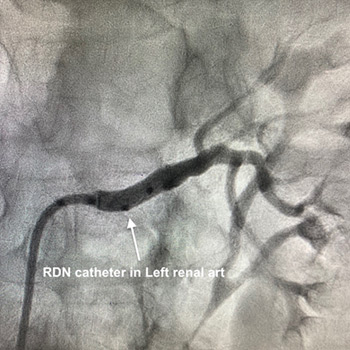

Renal denervation (RDN) is a catheter-based technique where a catheter is placed in the renal arteries (blood vessels that supply the kidneys) and either radio-frequency or ultrasound is used to burn the nerve endings surrounding the kidney arteries. The procedure is done under local anesthesia via a small pin hole in the groin. A small catheter is placed in the kidney blood vessel and after confirming the location with use of dye, a tiny wire with electrodes is inserted into the blood vessel and radio-frequency energy is delivered to the walls of the blood vessel. The procedure itself is very safe and can take up to 1 hour. The patient can be discharged the next day and can go back to normal life as before.